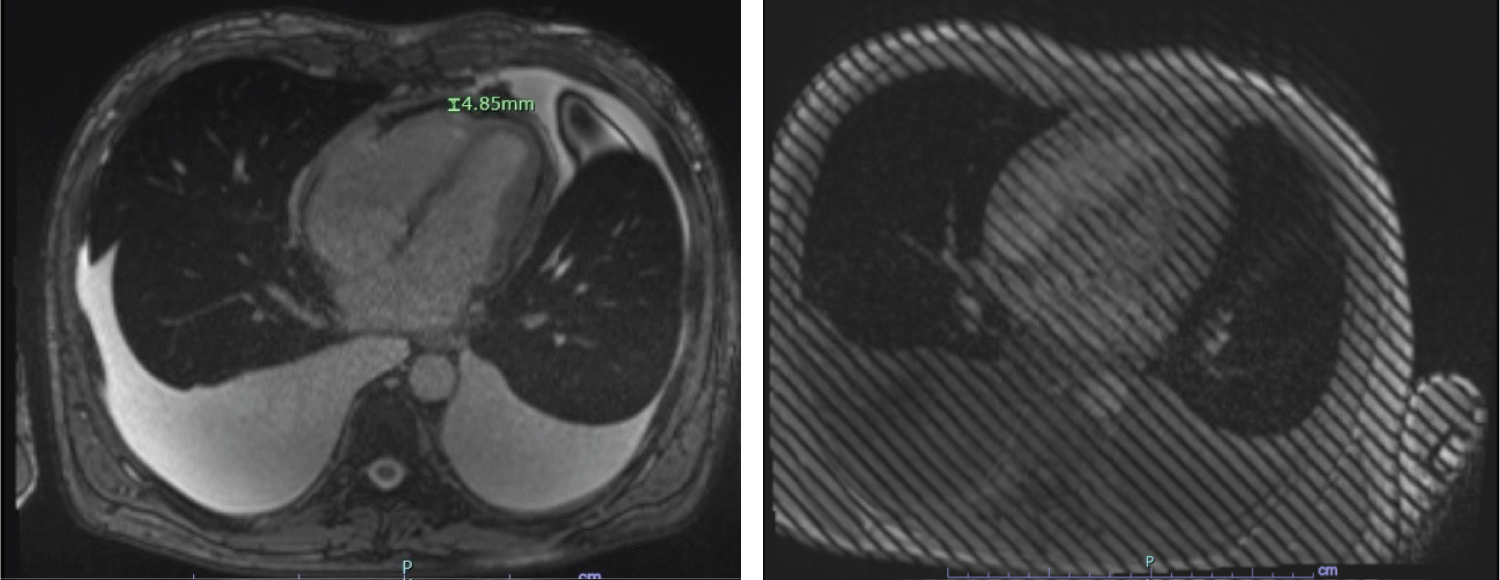

A Thoracentesis was performed revealed transudative pleural fluid, negative for malignancy and negative AFB culture. Serum ANA and anti-ds-DNA levels were normal. Viral serologies including HIV were nonreactive. Transthoracic echocardiogram revealed normal left ventricular ejection fraction (LVEF) of 55%, thickened pericardium with evidence of myocardial-pericardial tethering of left ventricular apical segments and signs of ventricular interdependence. There was leftward deviation of the interventricular septum during early diastole followed by “bounce back” or rightward deviation with late diastolic filling due to the lack of pericardial compliance, also known as “septal bounce”, highly suggestive of constrictive pericarditis (Figure 1 and Video 1).

Figure 1: M-mode echocardiogram showing interventricular dependence with inspiratory bulge of the interventricular septum from right to left (downward arrow) and left to right bounce with expiration (upward arrow). View Figure 1

Further work up was performed including cardiac catheterization (Figure 2). This revealed normal coronary arteries and various findings consistent with CP. The simultaneous LV and Pulmonary capillary wedge pressure (PCWP) tracing revealed discordance between the intra- and extra-pericardial pressures. This was due to limited transmission of respirophasic changes in intrathoracic pressure across the thickened pericardium to the cardiac chambers, resulting in a much greater variation in PCWP tracing with respiration compared to LV pressure tracing. The intracardiac pressure tracings also revealed square root sign and equilibrium or near-equilibrium of left and right diastolic pressures. Cardiac MRI (CMR) further reaffirmed the findings of pericardial thickening, apical pericardial tethering, and ventricular interdependence (Figure 3 and Figure 4).

Figure 3: A) CMRI showing 4.85 mm pericardial thickening; B) Tagged cine MRI showing adhesion of pericardium to myocardium. View Figure 3